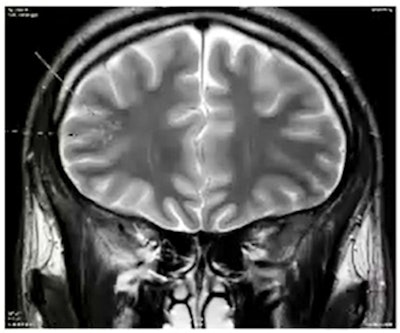

Pathologies induced by taking toxic substances, such as methotrexate toxicity. Neurotoxicity related to methotrexate can result in a range of acute and chronic leukoencephalopathies, and permanent neurological deficits may be unilateral or bilateral. Courtesy of Dr. Riyad Hanafi, CHU de Lille, and JFR 2021.

Pathologies induced by taking toxic substances, such as methotrexate toxicity. Neurotoxicity related to methotrexate can result in a range of acute and chronic leukoencephalopathies, and permanent neurological deficits may be unilateral or bilateral. Courtesy of Dr. Riyad Hanafi, CHU de Lille, and JFR 2021.The problem is that there is no reliable objective diagnostic tool, and diagnosis often relies on subjective clinical suspicion, which lacks reproducibility, he added.